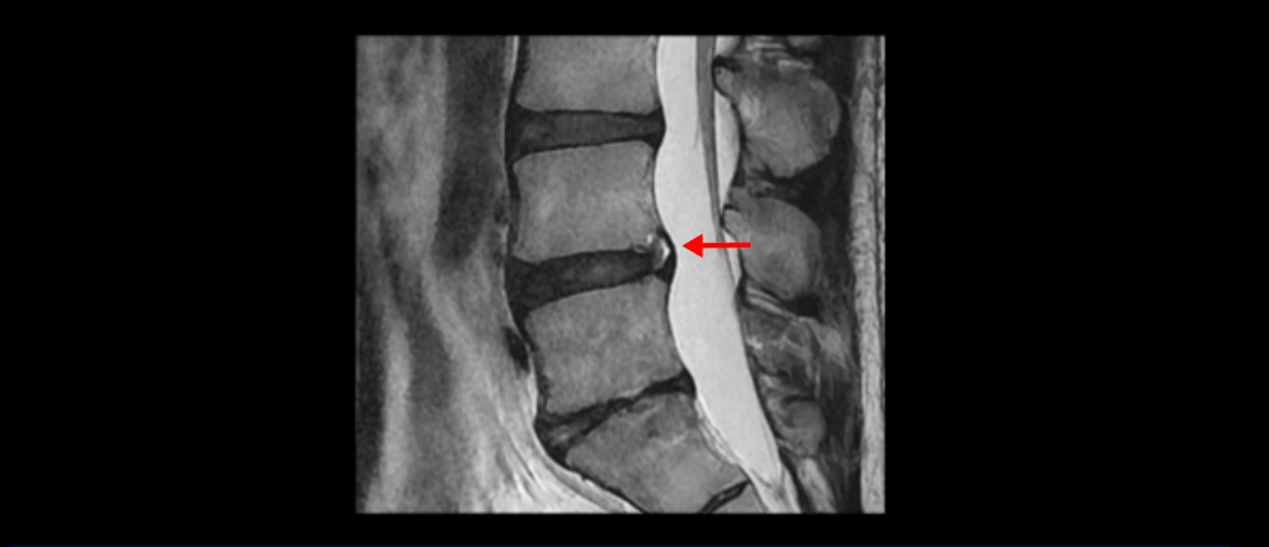

그런데 이분의 증상과 MRI가 전혀 일치하지 않는데, 왜 그런지 지금부터 자세히 설명드립니다. 이분 증상은 앉으면 엉치와 허리가 심하게 아파 10분 이상 앉는 게 어렵고 양쪽 발가락이 앉아있을 때나 누워있을 때 다 저립니다. 걸을 때도 아파서 10분 걷기도 어렵습니다. MRI를 마디마디 살펴보면 1번 2번은 오른쪽으로 살짝 밀려나온 디스크가 있지만 전혀 심하지 않고, 뒤에 또 설명하겠지만 최근에 밀려나온 급성 디스크가 아니고 오래된 디스크로 판단됩니다.

2번 3번도 비교적 디스크 상태는 좋고 신경 구멍 넓이도 아주 넓습니다.

3번 4번도 마찬가지로 디스크상태 좋아 보이고 신경 눌림 전혀 없어 보입니다.

4번 5번은 가운데로 섬유륜이 찢어져서 디스크가 살짝 밀려나와 있지만 역시나 최근에 찢어지고 밀려나온 걸로 판단되지 않고 오래 전에 찢어진 흔적으로 보입니다.

왜 최근에 찢어진 급성이 아니고 오래된 거라고 하는지 이 부분도 뒤에 한꺼번에 설명 드리겠습니다.

5번 1번 역시 가운데로 디스크 조금 밀려 나와있지만 신경 공간 넓이는 아주 넓어서 신경 눌림 있을 거라고 예상이 안됩니다.

앞서 1번 2번, 4번 5번, 5번 1번의 디스크가 찢어지고 조금 밀려 나온 게 최근에 찢어진 게 아니고 오래된 걸로 보인다고 말씀 드렸죠. 왜 그럴까요? 만약 급성으로 찢어진 것이라면 아주 심한 디스크성 통증이 있겠죠. 기침이나 재채기를 하면 심하게 아프고 허리를 조금만 구부리거나 비틀면 아주 날카로운 통증들이 생길 겁니다. 그런데 이분은 이런 증상이 전혀 아닙니다. 또 디스크의 밀려나온 정도도 전혀 심하지 않기 때문에 이분이 가지고 계신 양쪽 다리 저림, 특히 이분은 누워있을 때도 양쪽 발이 발가락까지 쑤신다고 하는데 이정도 디스크 때문에 그런 증상은 생길 수가 없는 겁니다. 이처럼 이분의 가벼운 디스크 탈출은 이미 오래 전에 진행되었고 섬유륜 자체는 이미 아문 상태인데도 디스크내장증을 진단받은 환자들 중에는 본인이 섬유륜 파열 환자라고 끝까지 믿는 분들이 많습니다. 다시 말하지만 디스크내장증이라는 진단을 받은 환자들을 보면 거의 전부 다 섬유륜 파열 증상이 아닙니다. 증상이 완전히 다릅니다. 진단이 애초에 잘못되면 어떤 치료를 받아도 좋아질 수 없습니다.